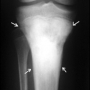

Kemiğe bitişik dokulardan çıkan ve kemiğin etrafını sararak yavaş yavaş büyüyen bir osteosarkom türüdür. Ancak ilerlemiş aşamalarda kemik dokusunun içine girer. Histolojik olarak düşük dereceli bir osteosarkomdur. Klasik osteosarkoma göre daha ileri yaşlarda görülür (20-40 arası). Bu yapı ve davranış değişiklikleri, tanı ve tedavide de farklılık yaratır. Tamamen selim bir oluşum olan myositis ossifikans (kas içi kemikleşme) ile karıştırılmamalıdır.

Tedavi, yerleşim ve biyolojik davranışa göre özellik gösterir. Kemiğin çevresini ve komşu dokuları tuttuğu için sıklıkla kemiğe komşu damar ve sinir yapılarını da sarar. Cerrahide bu mutlaka dikkate alınmalıdır.

Düşük dereceli bir osteosarkom olması nedeniyle vücudun başka bölgelerine sıçraması (metastaz) daha geç ve güç olur. Ancak bulunduğu yerde tekrarlama (lokal nüks) özelliği klasik osteosarkoma göre daha fazladır. Üstelik kemoterapiye de duyarsızdır. Bu nedenle cerrahi tedavinin daha kolay ve güvenli bir şekilde yapılabilmesini sağlayan kemoterapinin tedavide yeri yoktur. Tek tedavi şansı, tümörün emniyetli sınırlarla çıkartılmasıdır. Gerekirse uzvu besleyen ana damarlar da çıkartılmalı ve değiştirilmelidir. Yetersiz cerrahi, tümörün tekrarlamasına, giderek derecesinin yükselmesine ve metastaz riskinin artmasına yol açar.